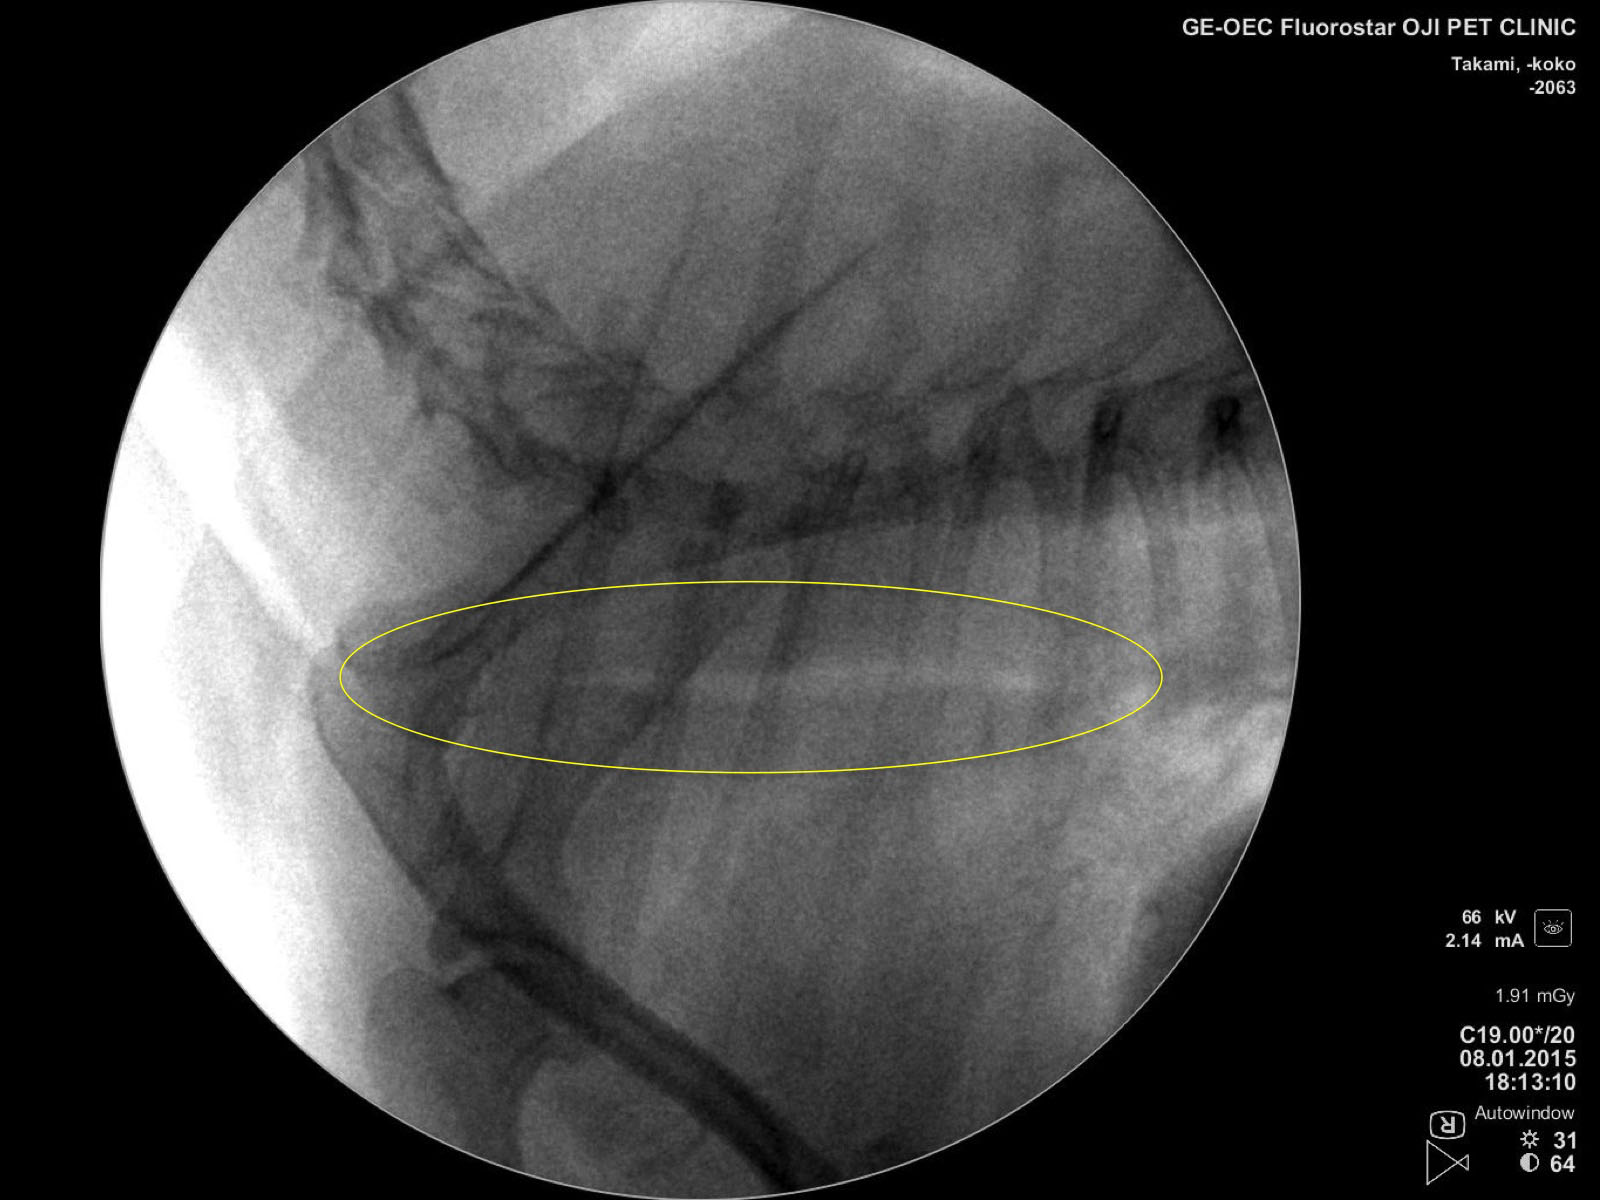

夜眠る事ができないくらい咳がひどいとのことで来院。 Cアームで撮影すると、

頚部から胸腔内の気管が潰れ、虚脱している様子が分かります。

動的に評価する事で吸気、呼気の気管の状態をしっかりと把握することができます。